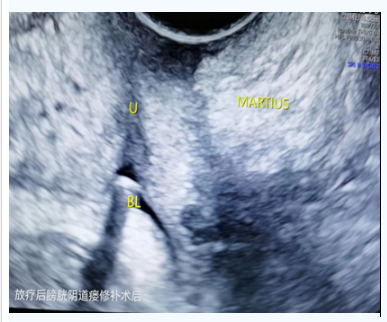

放疗后膀胱阴道瘘修补+Martius组织瓣移植术+全阴道封闭术。

术后随诊:

术后留置导尿管4周,拔除尿管,恢复自主排尿。

(放疗后膀胱阴道瘘修补术后)